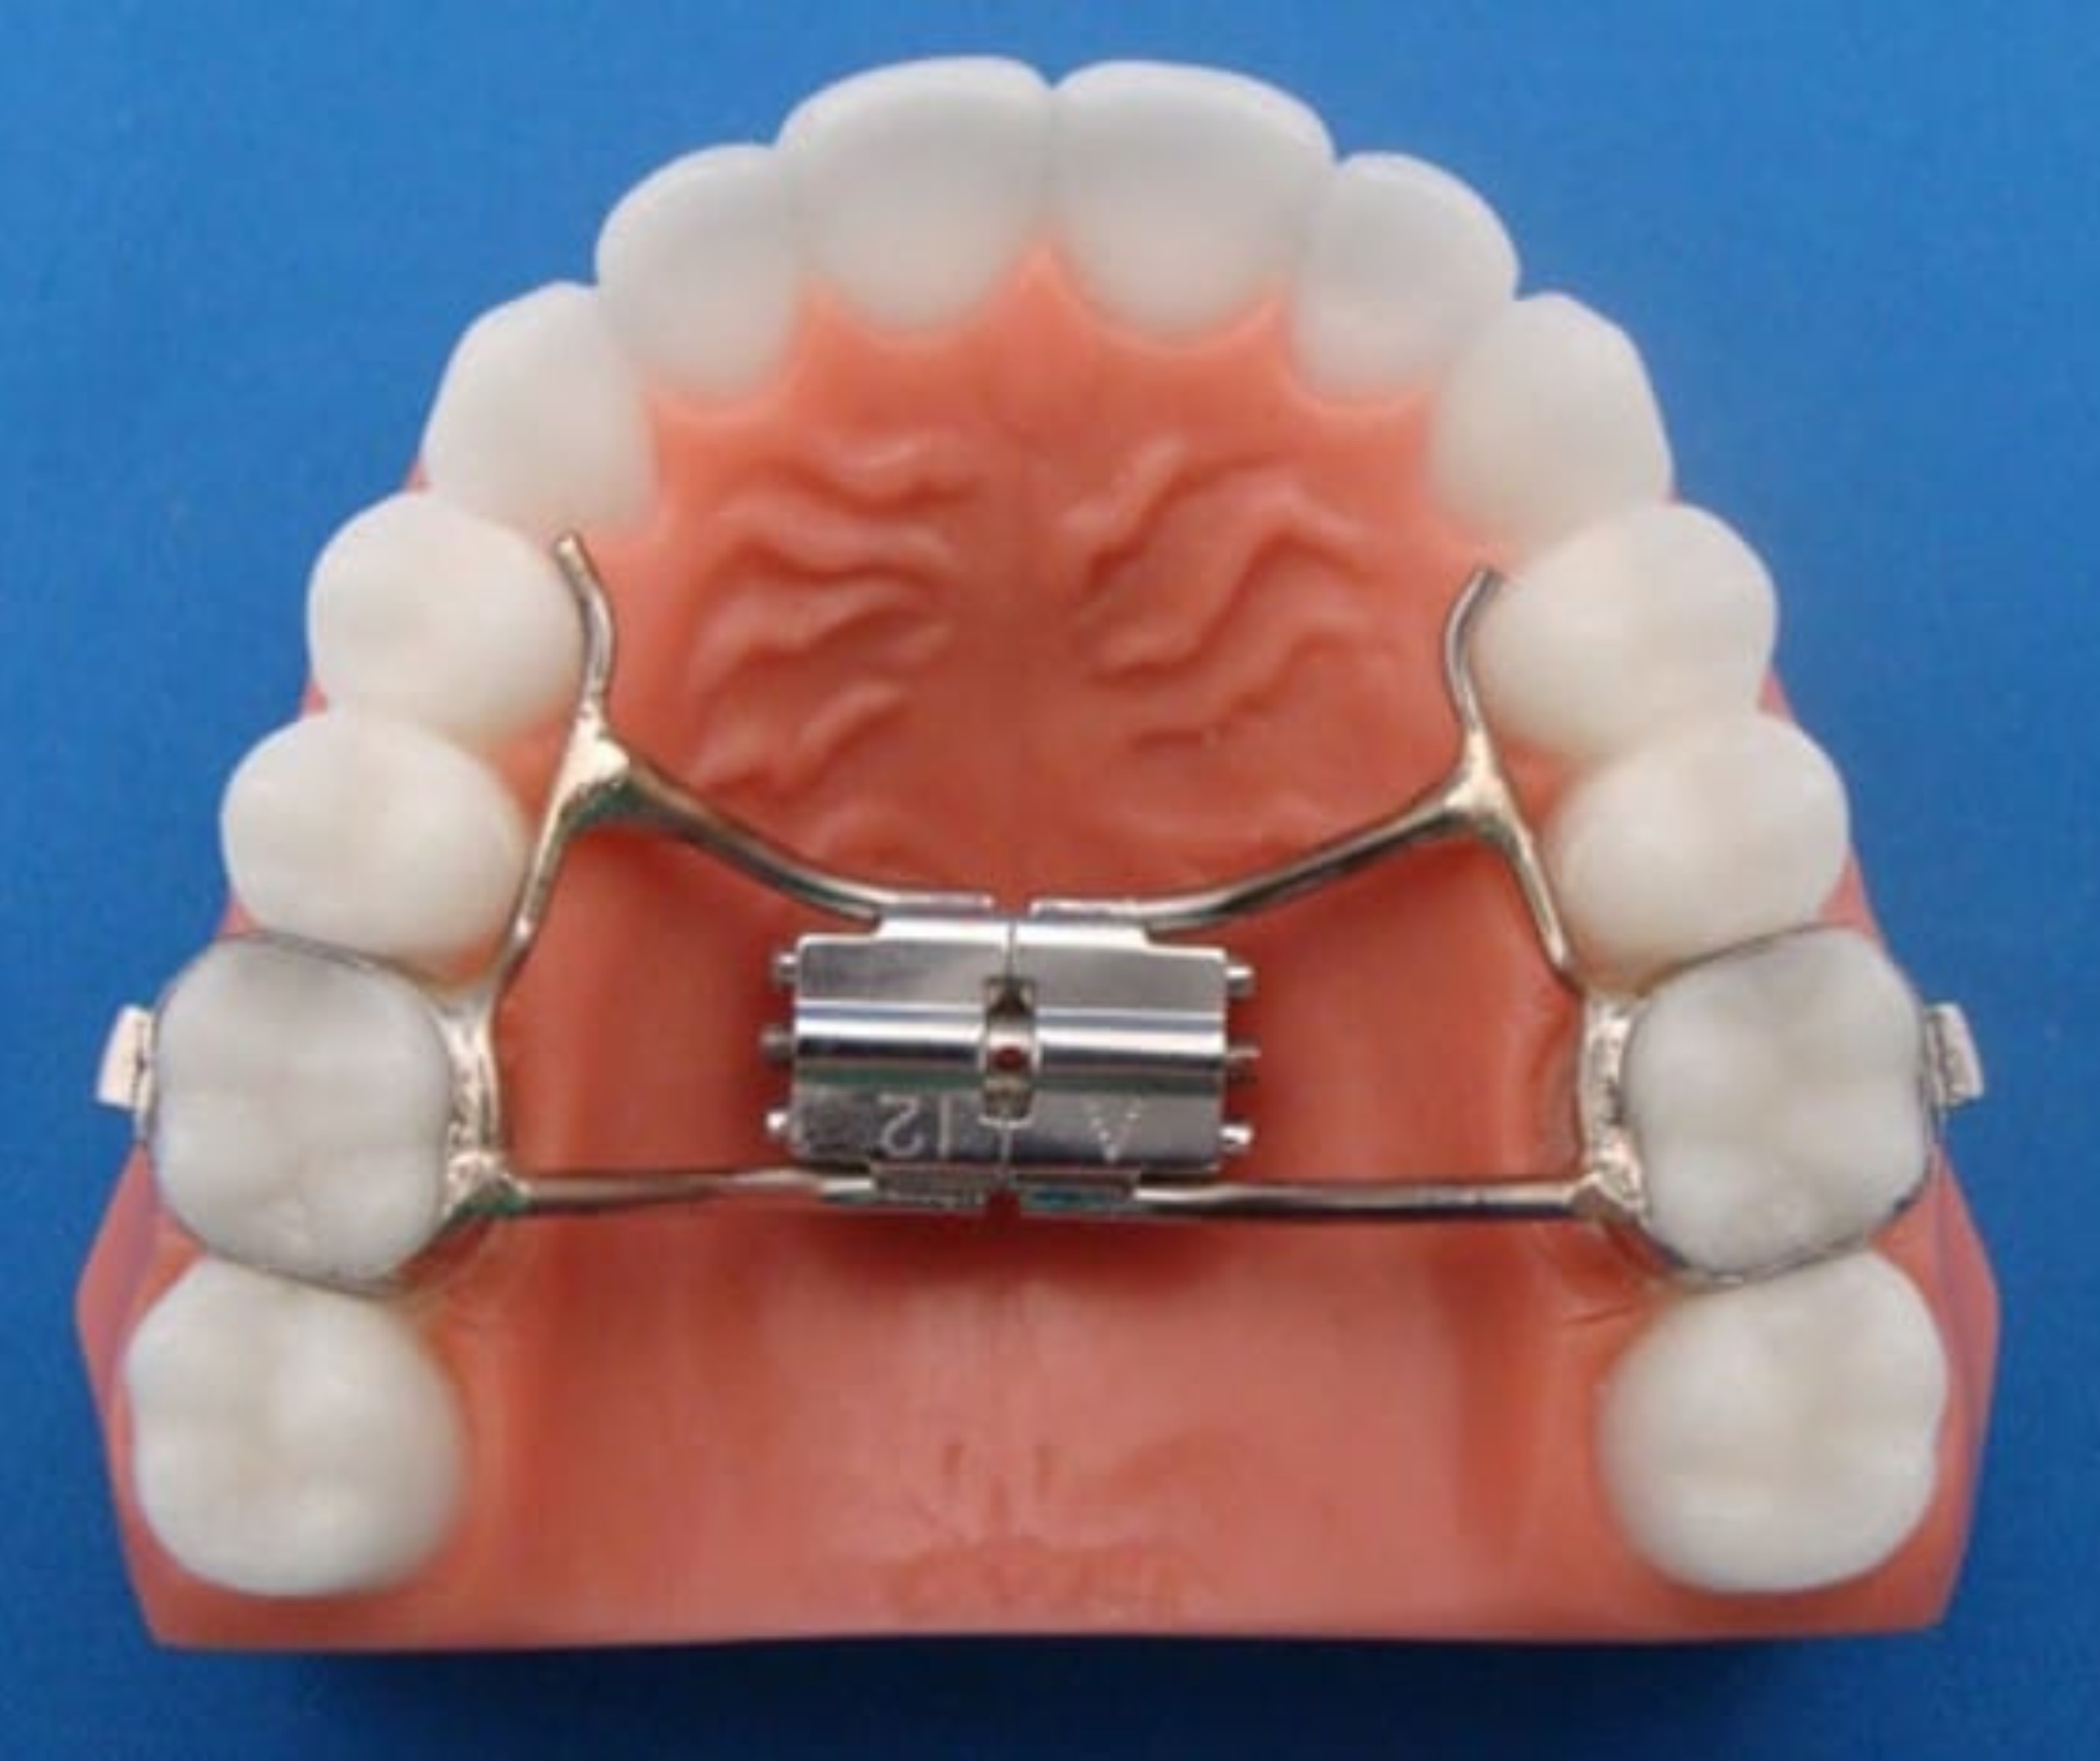

Pediatric & Adolescent Orthodontics

Early intervention can guide jaw growth and prevent future complications.

You will learn about:

- Growth monitoring

- Space maintainers and expanders

- Phase I and Phase II treatment

- Communication strategies for younger patients

- Parental education

Orthodontic assistants must understand both clinical mechanics and patient psychology.